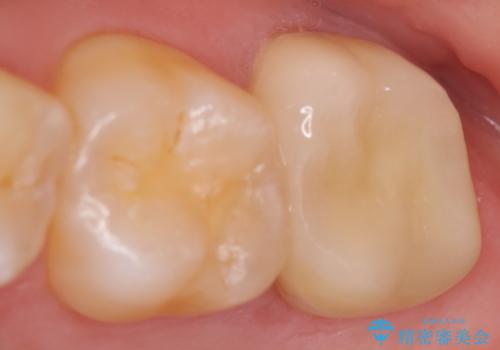

- 他院にて左下6番目の歯の根管治療を行っていたが、痛みが引かず抜歯を提案されたため、何とか歯を残せないかと当院にいらっしゃった方の症例です。

顕微鏡下で精密根管治療を行い、症状の緩解を確認後、オールセラミッククラウンによる補綴を行いました。